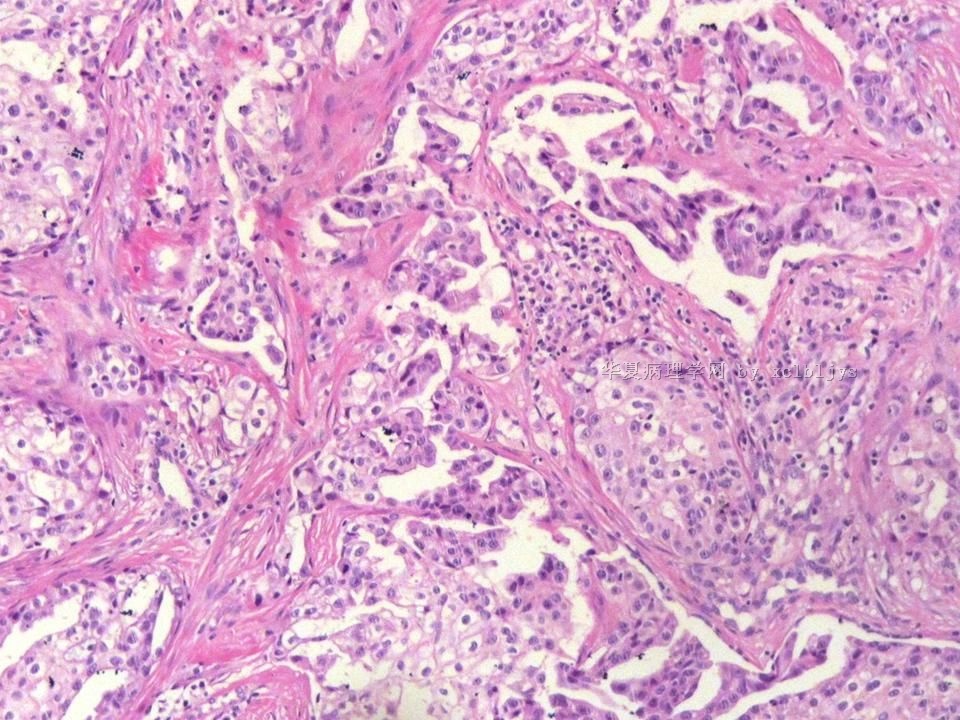

姓    名: ××× 性别:  男 年龄:  56

左锁骨上肿块三月余,手术切除。

蚕豆大肿块,包膜较完整,切面灰红色,质软。

• 左锁骨上肿块(IHC)图2

图2

转移癌

首先考虑甲状腺或肺来源

转移性腺癌。清查胃、肺等处有无原发灶。

转移性腺癌,请查消化道

免疫组化结果:TTF-1(+),CK7(+),CK20(-),TG(-)。临床近一步检查,肺未见肿块,左甲状腺发现肿块,目前仍未处理。

从形态结构看,有腺泡也有乳头结构,倾向转移性肺腺癌。